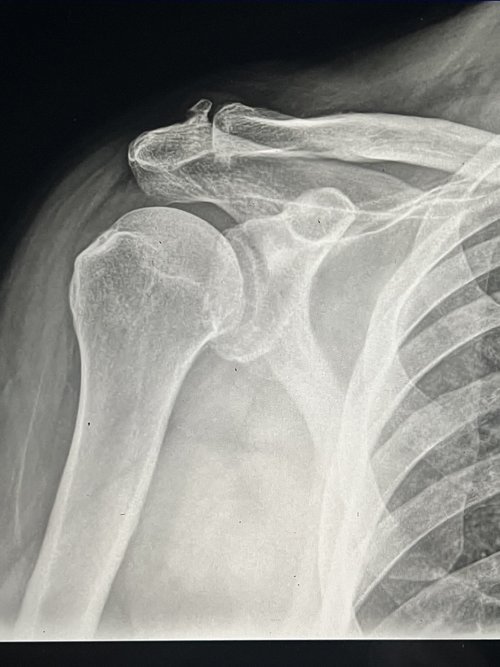

X-ray image of a shoulder joint, including the humerus, scapula, and clavicle.

X-Ray & ECG

All x-rays are performed in house using the latest digital x-ray technology providing for rapid diagnoses and treatment of many conditions.